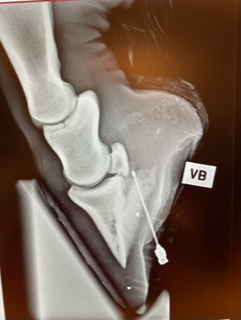

Før undersøkelsen må høvene gjøres rene slik at ikke gjørme og grus skaper forstyrrelser i bildet. Ved undersøkelse med tanke på skoing og/eller beskjæring bør bildene tas med skoene på. Dette gir opplysninger om hovens overrulling og balanse. Det er vanlig å merke hoven med røntgentett materiale på noen holdepunkter, for eksempel på hovveggen, på strålespissen og ved kronranden.

Avhengig av hva som er hensikten med undersøkelsen, kan man ta ulike bilder av hoven. Dersom det mest relevante er beskjæring og/eller skoing, vil sidebilder være det viktigste, gjerne i kombinasjon med bilde rett forfra/bakfra. Man kan også fokusere på hovseneben, hovbensgrener, draktbruskforbeining, hovnbensbrudd eller andre problemstillinger, og da kan det være nødvendig å komplettere med bilder fra andre vinkler.

Ved spikertramp er røntgenbilder gull verdt for å kunne bedømme skadens omfang.

Når bildene er tatt, kan de behandles digitalt, før de oversendes til eier og hovslager. Det er spesielt interessant å benytte måleverktøy ved behandling av bildene, som en veiledning på hvordan hoven bør korrigeres. Ved problemer som for eksempel forfangenhet, vil også noen målinger kunne gi en pekepinn om alvorlighetsgrad og prognose.

Flere målinger kan være akutelle, dette avtales gjerne mellom hovslager og veterinær. Noen eksempler kan være hovvinkel, lengde på hovvegg i tå, lengde på hovvegg i drakt. Såletykkelse, hovveggstykkelse, hovbensvinkel og overrullingspunkt.